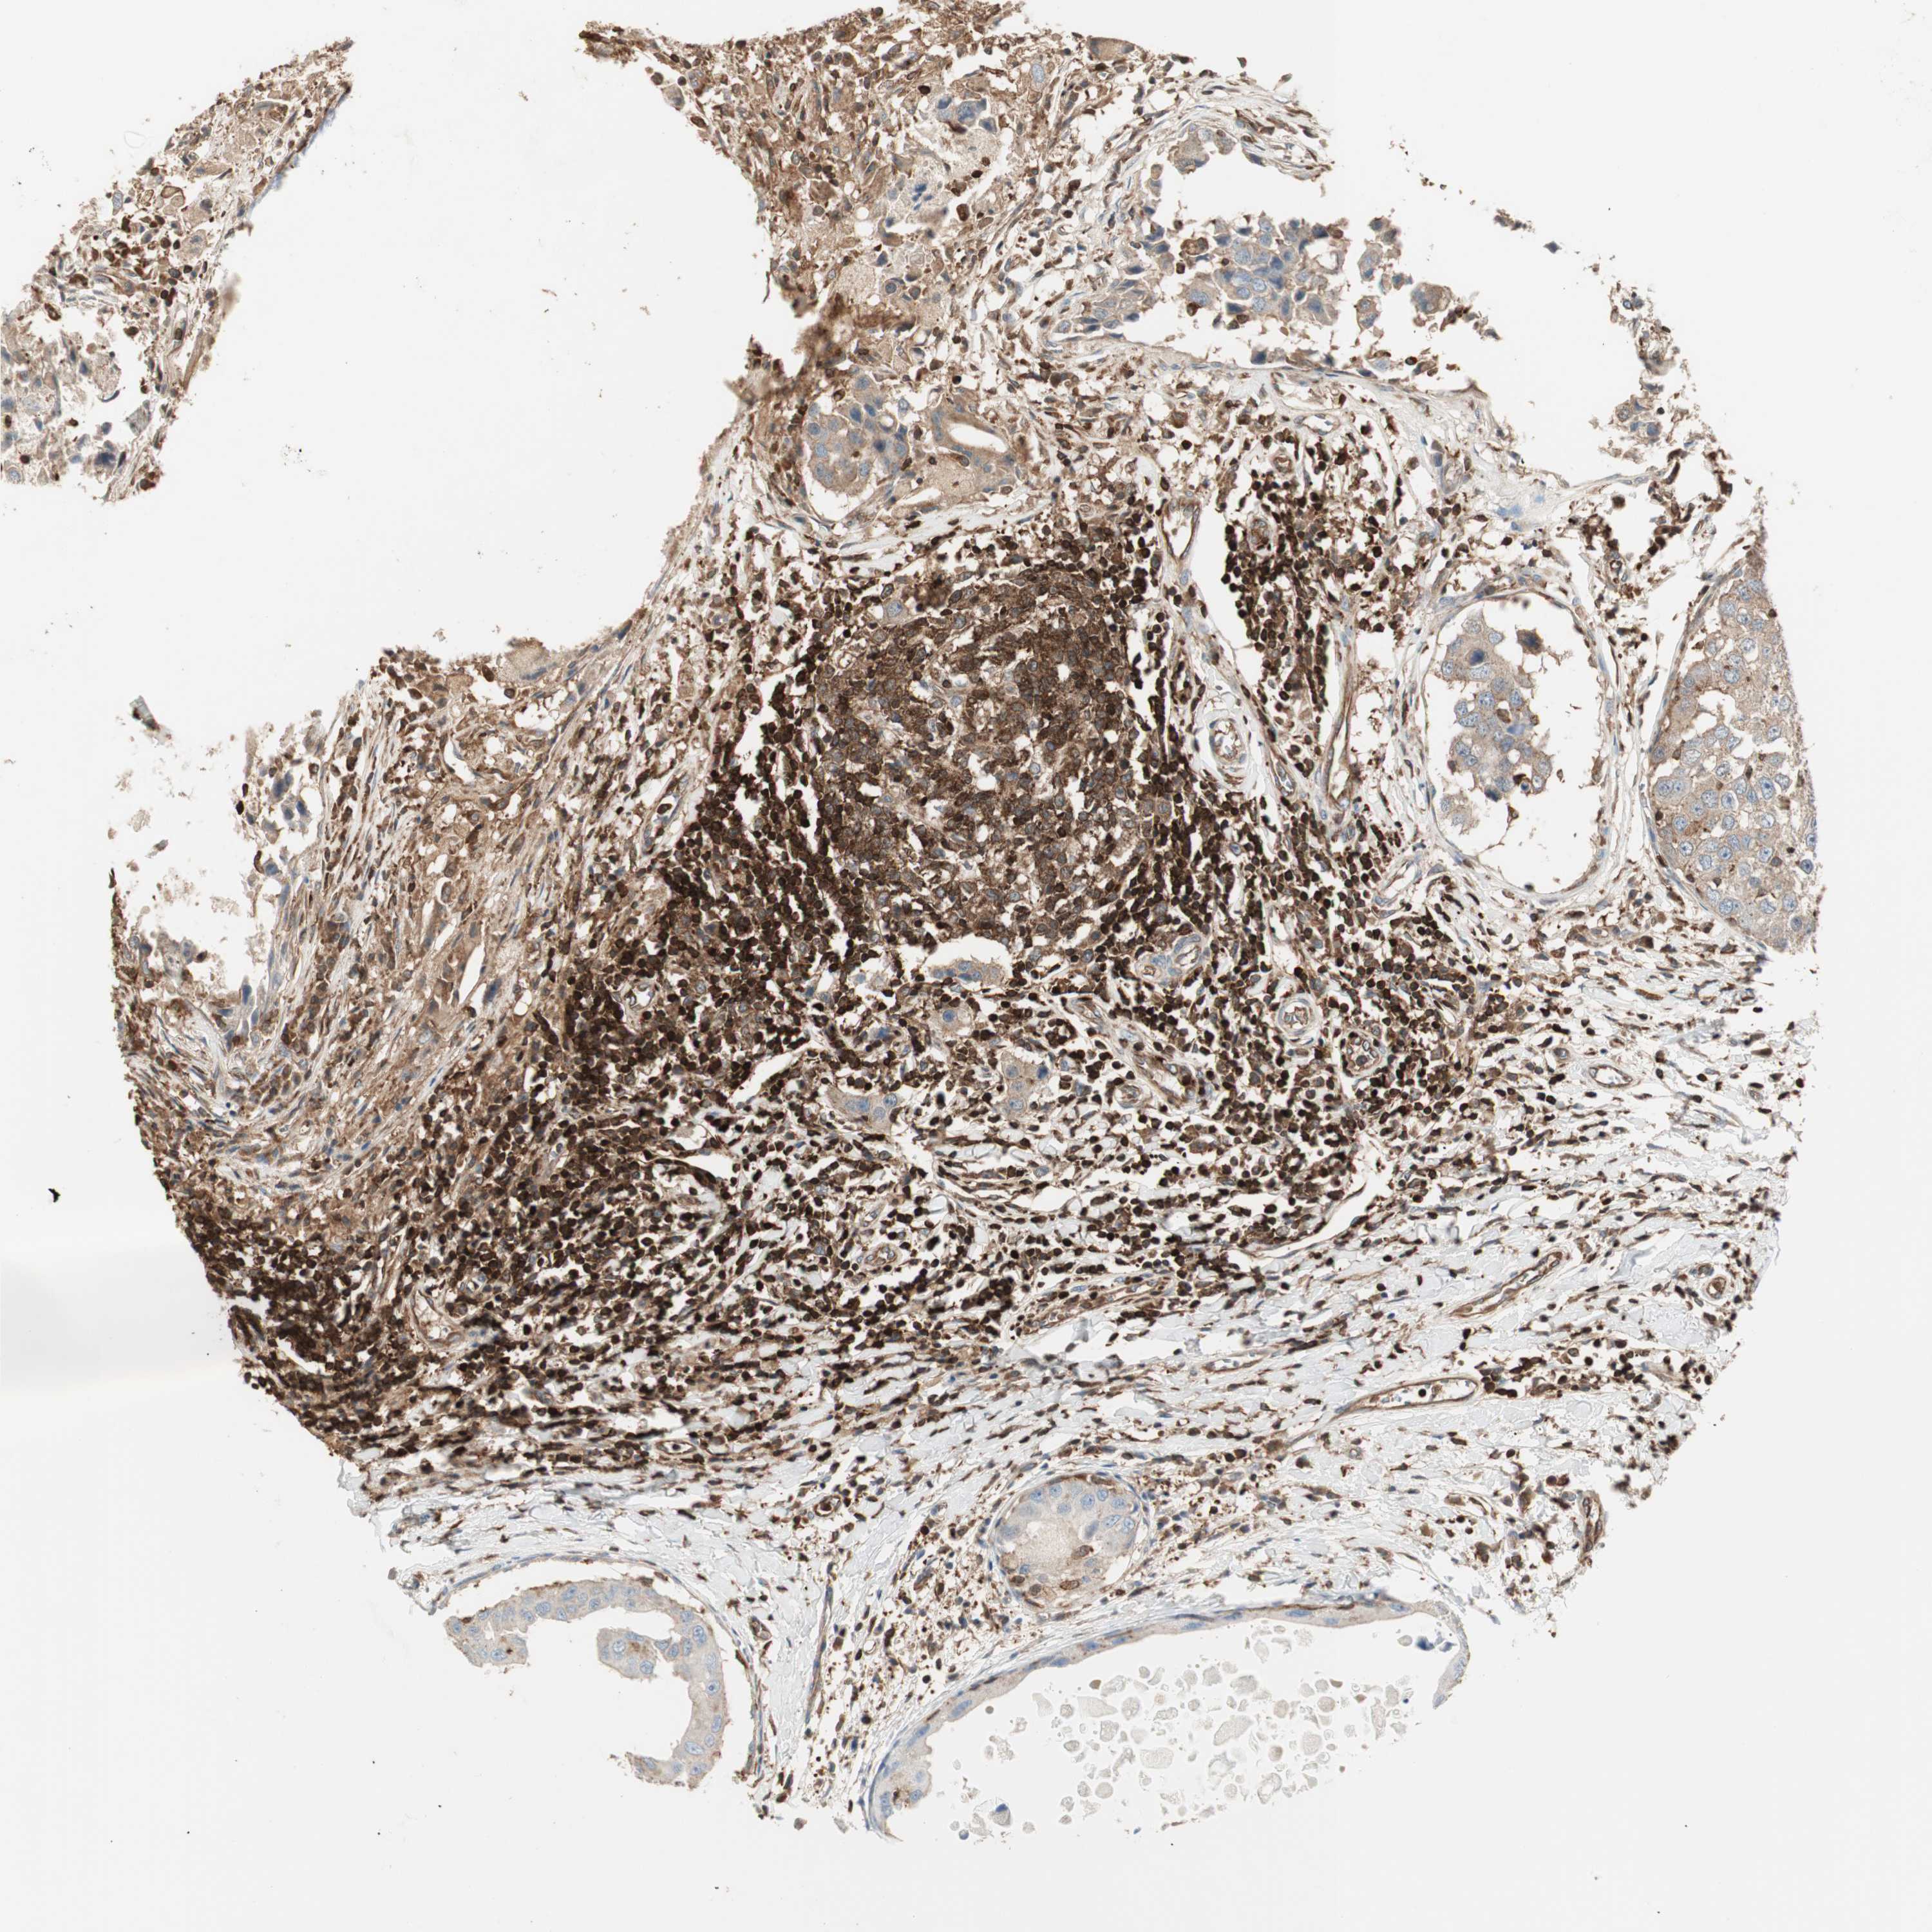

BRCA TCGA BRCA VALIDATION PROTEIN EXPRESSION